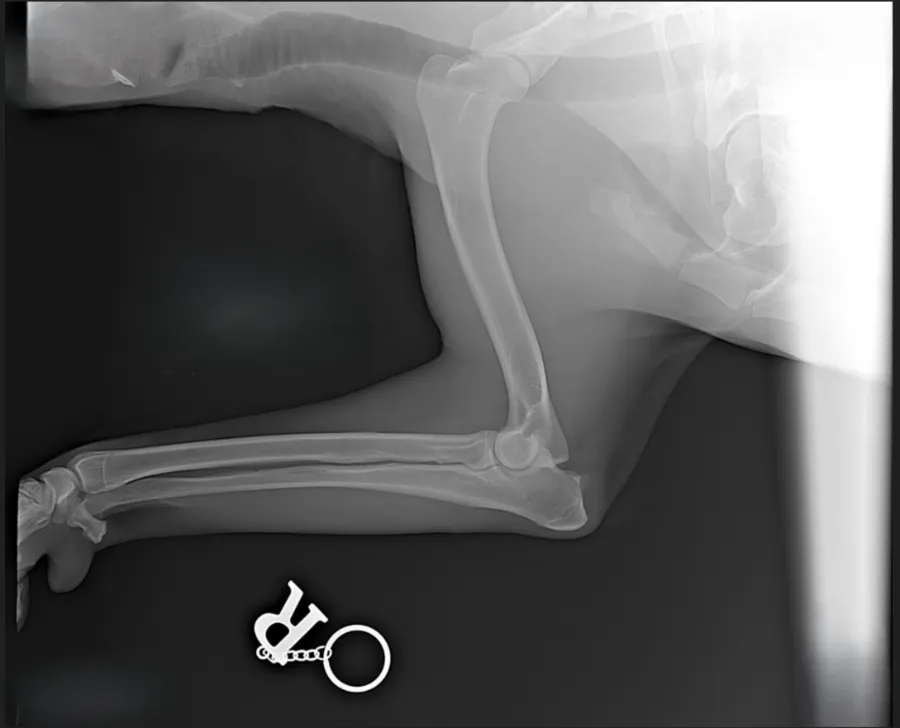

Единственным надёжным методом подтверждения является рентгенография тазобедренных суставов, проведённая опытным специалистом. Важно правильно уложить собаку под наркозом, поскольку неправильная позиция может исказить результаты исследования.

Для определения степени тяжести дисплазии используют международную классификацию FCI/РКФ:

- А — норма.

- B — лёгкое отклонение, допустимое для разведения.

- C — средняя степень отклонения.

- D — тяжелая форма, противопоказанная для размножения.

- E — крайне тяжёлая патология, показывающая полную невозможность нормальной жизнедеятельности.